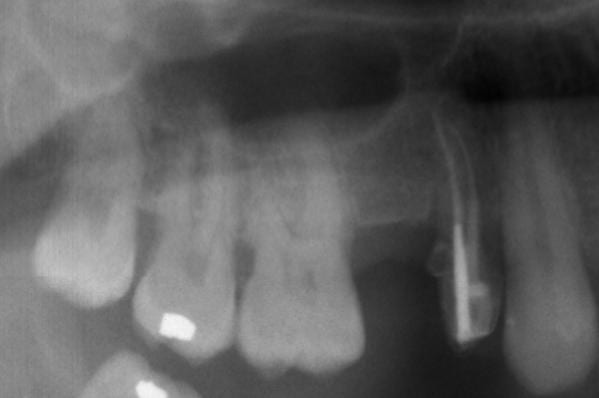

Mon premier Summers... (+ lazzara).

j'ai mis un implant de 4 x 9 avec récup de l'os de forage (peu) et du béta-TCP.

Nombreux sont ceux qui auraient mis du 11 mm, mais pour une première je me suis dit que "9 tiens valent mieux que 11, tu les auras" (...peut-être sans perforer..).

Merci pour vos commentaires.

nolive.